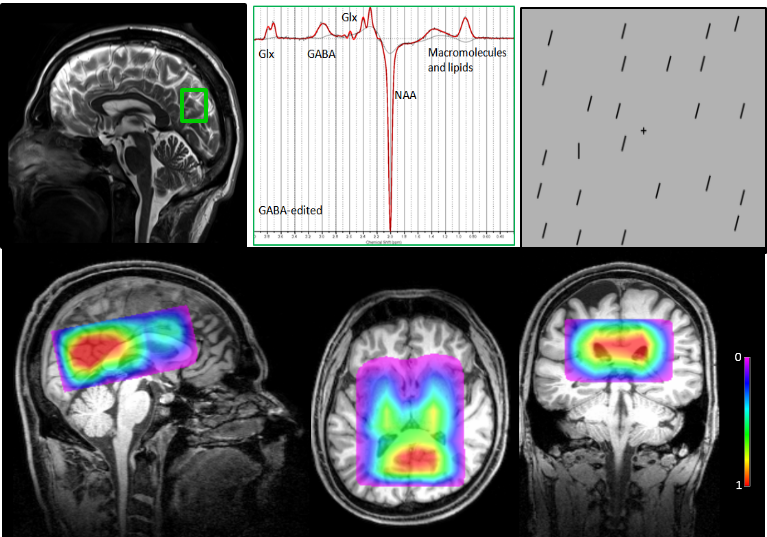

Top left:Single voxel GABA MRS voxel in the visual cortex; top middle: A typical GABA-edited spectrum; top right: visual stimuli for the subjects.

Bottom: A Novel 3D Multi-Voxel MRS Investigation of Autism using MEGA-LASER

Attention Strengths and GABAergic Function in Children with Autism